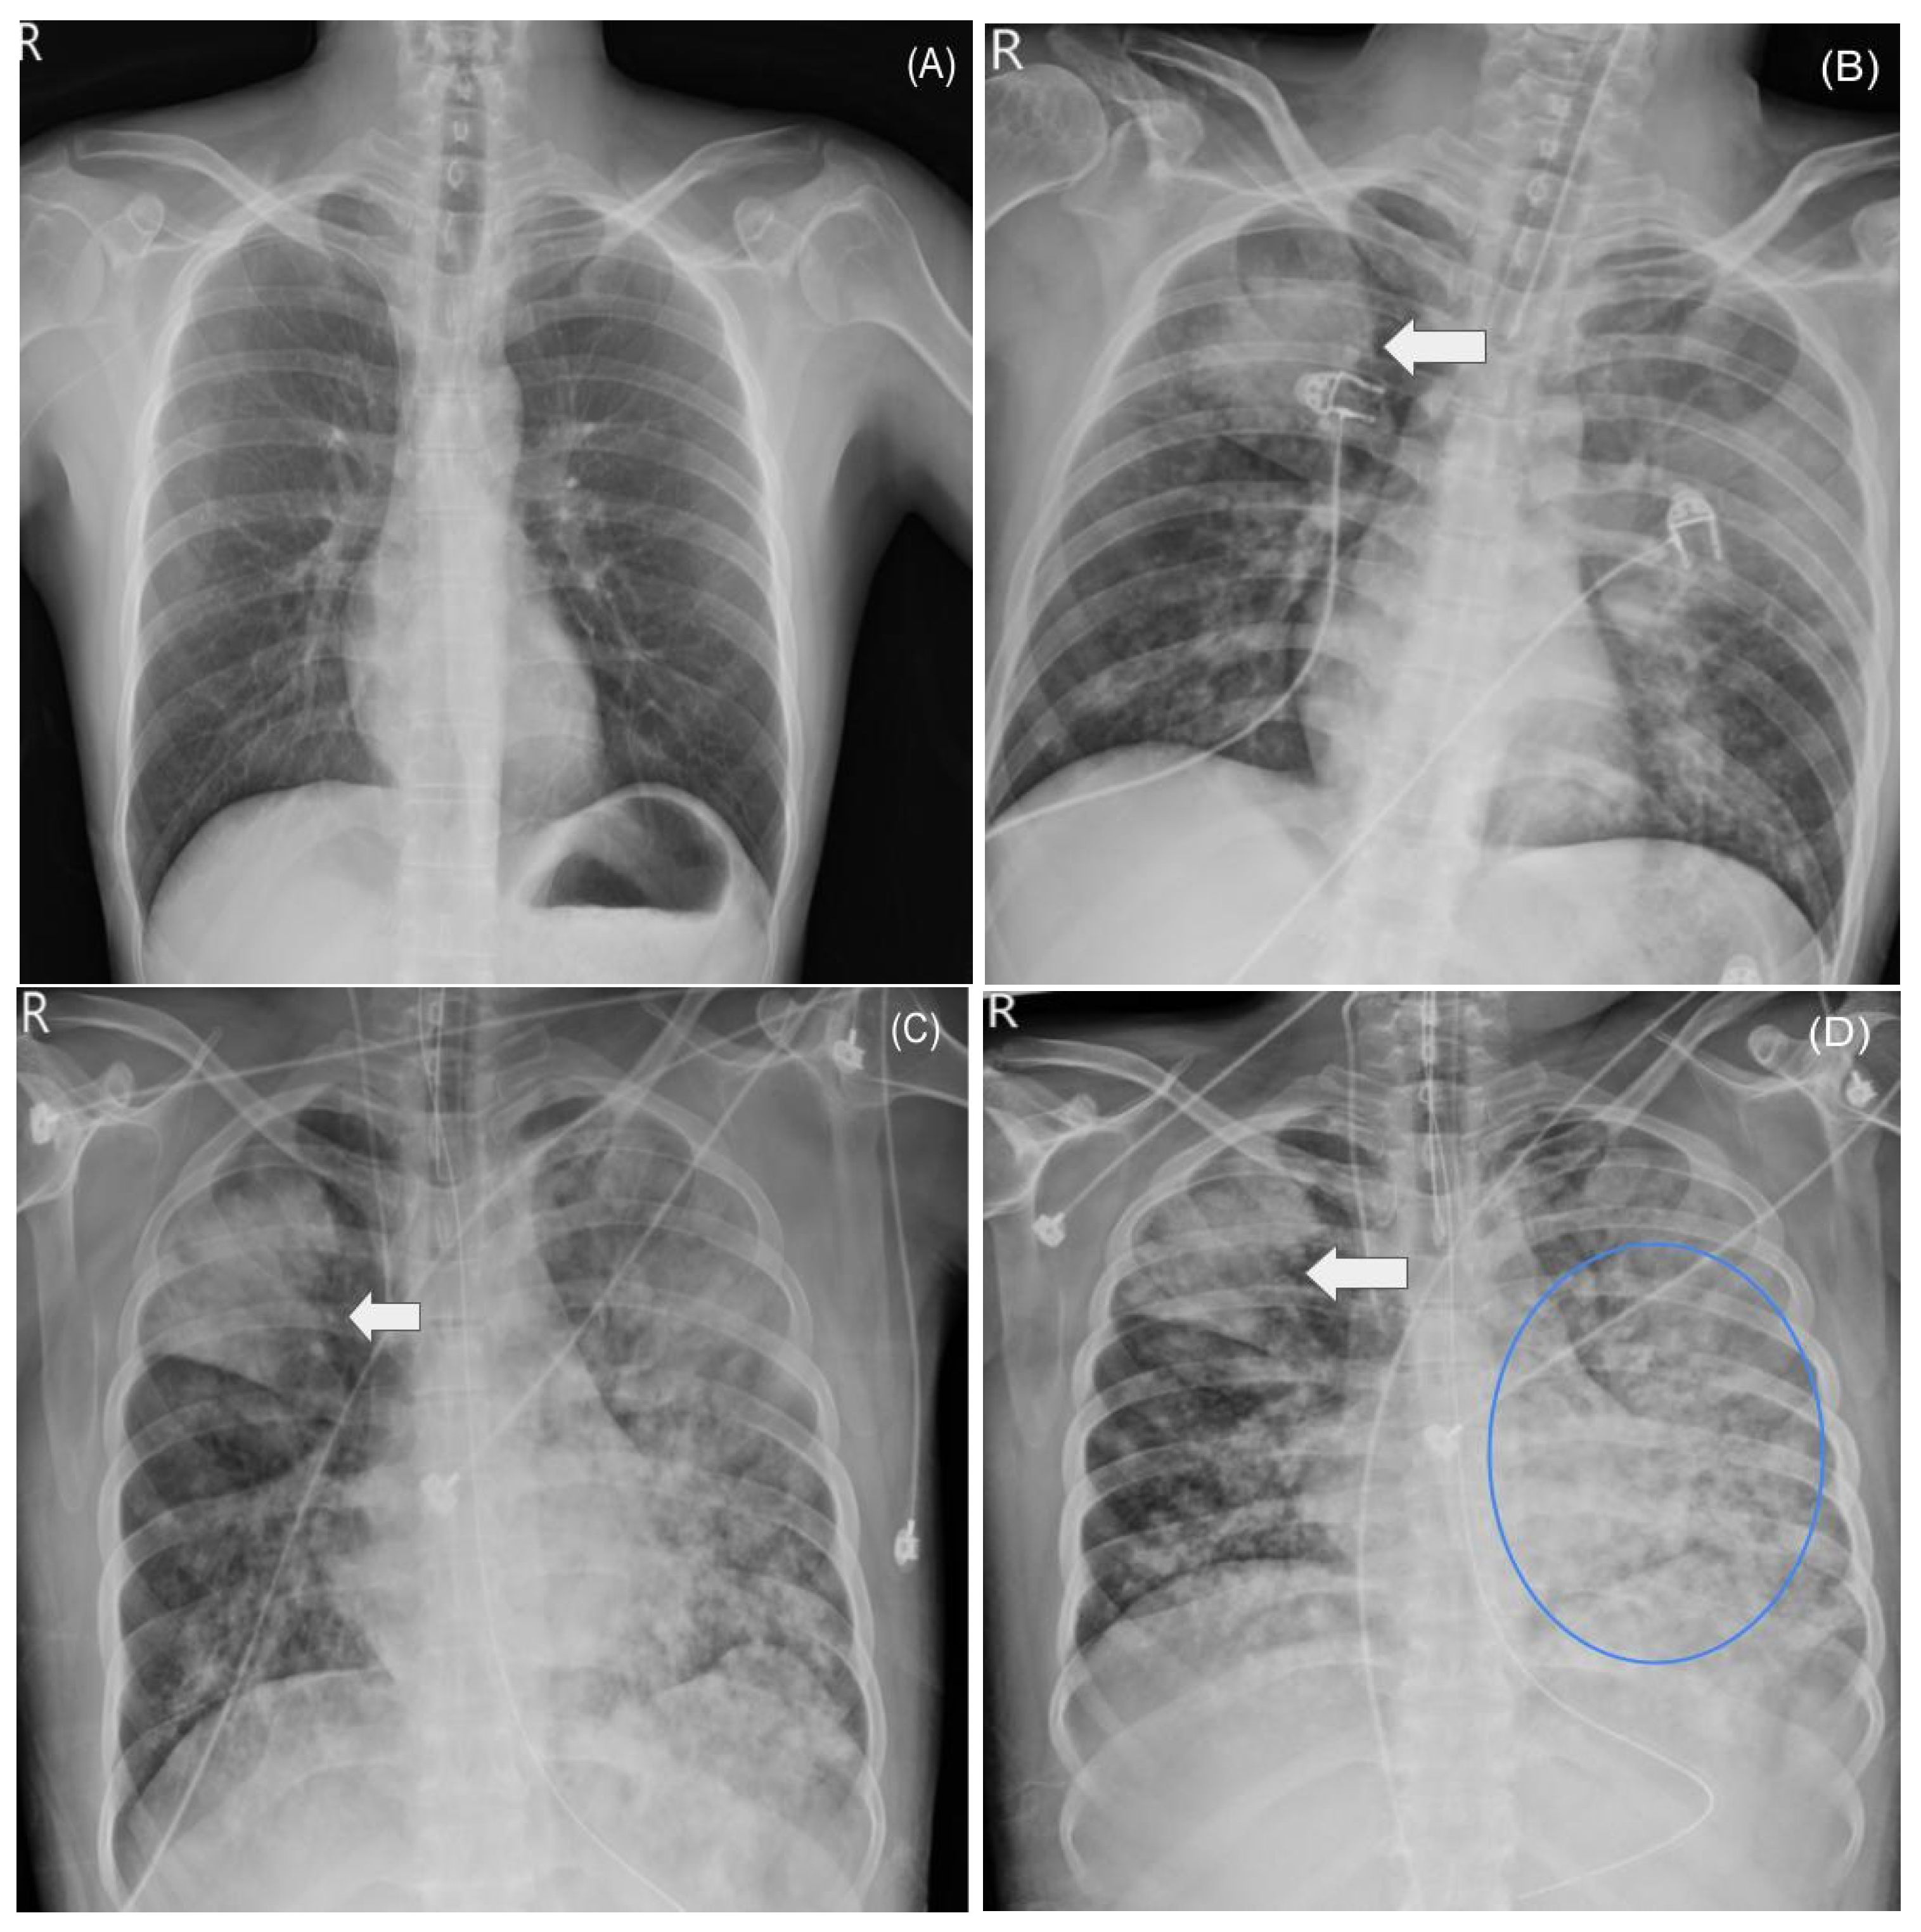

2.3. ICU Course and ARDS

3.1. Clinical Course